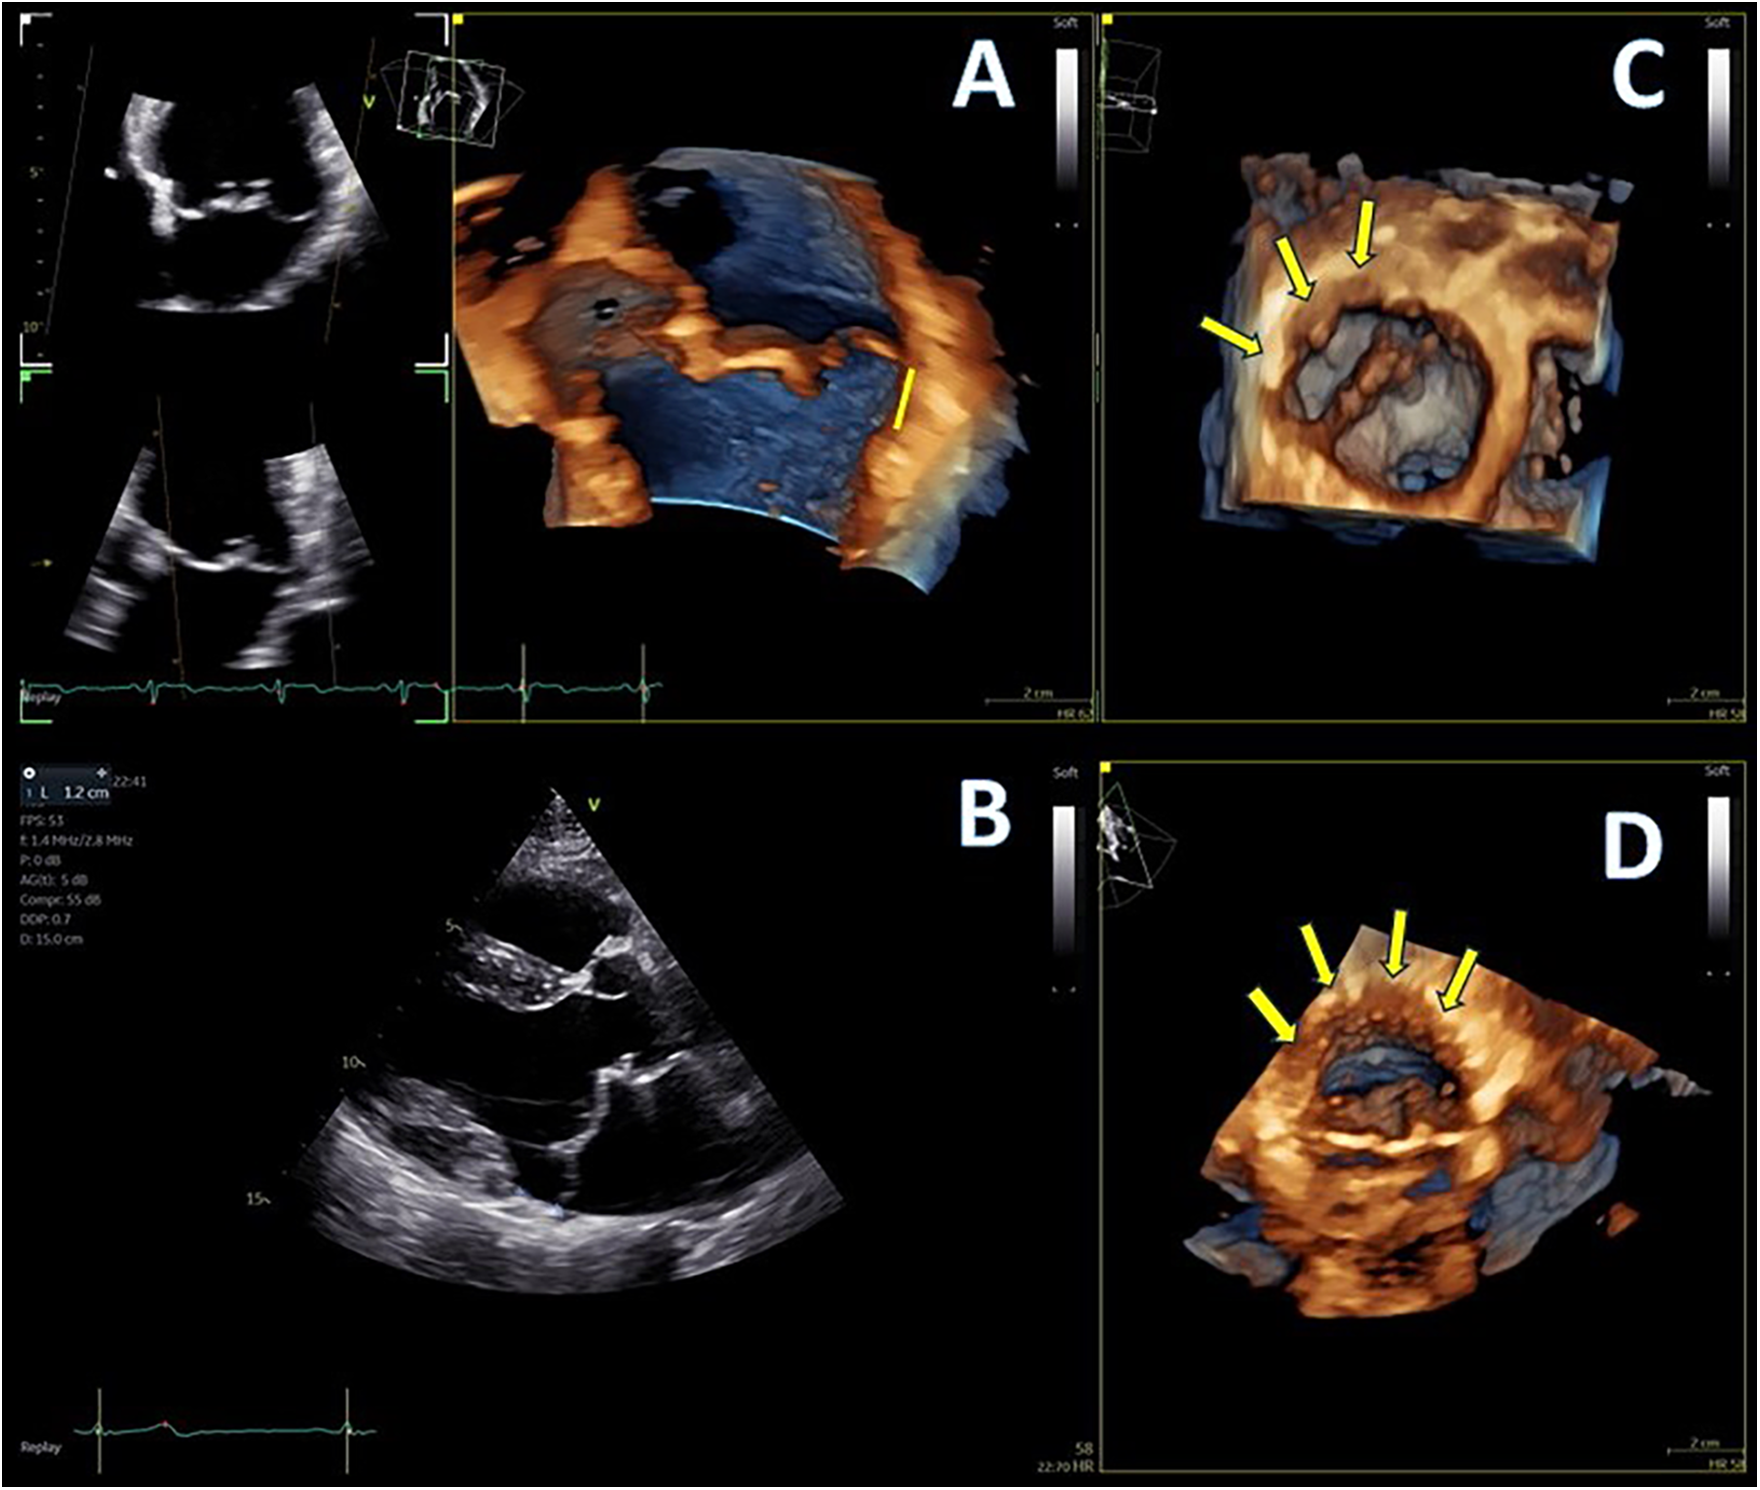

A 50-year-old male patient with mitral regurgitation (MR) and MAD previously diagnosed with CMR was referred to our clinic due to a recent syncopial episode. TTE revealed severely dilated left heart chambers (4D left ventricular end-diastolic volume (LVEDV) = 218 ml, left atrial volume index (LAVI) >48 ml/m2) with an LVEF of 57%, bileaflet prolapse of the mitral valve, severe MR [effective regurgitant orifice area (EROA) 60 mm2, regurgitant volume (RV) 117 ml], and a 12 mm displacement of the hinge point of the mitral annulus from the posterior ventricular wall (Figures 1A,B). Further complete 3D-TTE analysis of the patient was performed to demonstrate the imaging findings of MAD syndrome (Figures 1C,D). A previous CMR examination of the patient had reported LV dilatation with almost identical volumes and EF to TTE (EDV = 217 ml, EF = 59%), the presence of MAD of 10 mm displacement, and the presence of myocardial fibrosis of the basal inferolateral wall (Figure 2). Due to our protocol for patients with syncope, we performed a 24 h ambulatory electrocardiogram (ECG) that revealed episodes of monomorphic and polymorphic non-sustained ventricular tachycardia (Figure 2). In accordance with the management algorithm of the recently published EHRA and EACVI consensus document for MAD syndrome (15), the patient was treated with surgical mitral valve repair and implantable cardioverter defibrillator (ICD) implantation.

Figure 1

(A,B) Mitral annular disjunction (MAD) demonstrated by 4D and 2D transthoracic echocardiography (TTE), 12 mm of distance from posterior left ventricular (LV) wall, indicated with yellow line, and (C,D) extent of disjunction arc seen with two different orthogonal volume rendering views, indicated with yellow arrows.

Advanced mitral valve assessment was performed with the AutoMVQ method that provided the measurements of the leaflets and the annulus, using an apical four-chamber view, focused on the mitral valve with 4D zoom and a frame rate of >12 vps. By default, AutoMVQ creates the mitral valve model using a middle reference frame between end-diastole and end-systole. Since the requested information for MAD syndrome is the dimension changes between diastole and systole, we had to manually adjust the systolic and diastolic frames twice and provide two different mitral valve quantification (MVQ) models. A direct comparison of the systolic and diastolic models allows us to understand the dynamic annulus changes in MAD syndrome. In our patient, this method confirmed (1) the flattening of the saddle-shaped annulus during the systole and (2) the systolic expansion. In particular, the annulus area increased from 14.6 cm2 to 23.2 cm2, the perimeter from 13.7 cm to 17.2 cm, the anteroposterior diameter from 3.4 cm to 4.8 cm, and the commissural diameter from 4.2 cm to 5.5 cm. Meanwhile, the annulus height decreased from 11.4 cm to 7.0 cm (Figure 4). The disjunction arc of the valve was easily demonstrated by an “en face” 3D ventricular view of the mitral valve where the extent of the arc was assessed by measuring the circumference of the posterior annulus involved within the disjunction. Volume rendering views can reveal the actual part of the free posterior wall of the left ventricle that is separated from the annulus and the atrium (Figures 1C,D).

A standard 2D parasternal long-axis view was the first image that was used to confirm the presence of MAD syndrome by the “uncoupling” of the posterior ventricular wall from the hinge point of the posterior mitral annulus. A distance of more than 5 mm is usually considered to be diagnostic for the presence of MAD (14). 3D-TTE was able to provide detailed information about the presence and extent of the disjunction arc, the systolic expansion, and the flattening of the saddle-shaped annulus. The extent of the disjunction arc correlates with the severity of MR and the abnormal dynamics of the valve (6). It is well established from previous publications (6, 13, 24) that at the end-diastole, the annulus dimensions are at their maximum, with the anteroposterior diameter and annulus area presenting the greater change. Physiologically, the annulus contracts rapidly at the early systole and then starts to expand. In normal subjects, the end-systolic annulus area is smaller than the end-diastolic one (6). Patients with myxomatous valve disease have larger annulus dimensions, the valve expands even more at the late-systolic period, but the overall annulus area does not reach the end-diastolic measurements (6, 25). In MAD syndrome, on the other hand, the baseline dimensions of the annulus are increased. There is still early systolic contraction of the valve, but, afterward, there is overexpansion of the annulus, with dimensions that exceed the diastolic ones (25). Manual adjustments of the standard MVQ methodology were able to appreciate the systolic expansion and flattening of the annulus by measuring all annulus dimensions and height changes throughout the cardiac cycle. The two frames that we used were the end-diastolic and end-systolic ones to be in agreement with previous publications that analyzed the annulus dynamics.